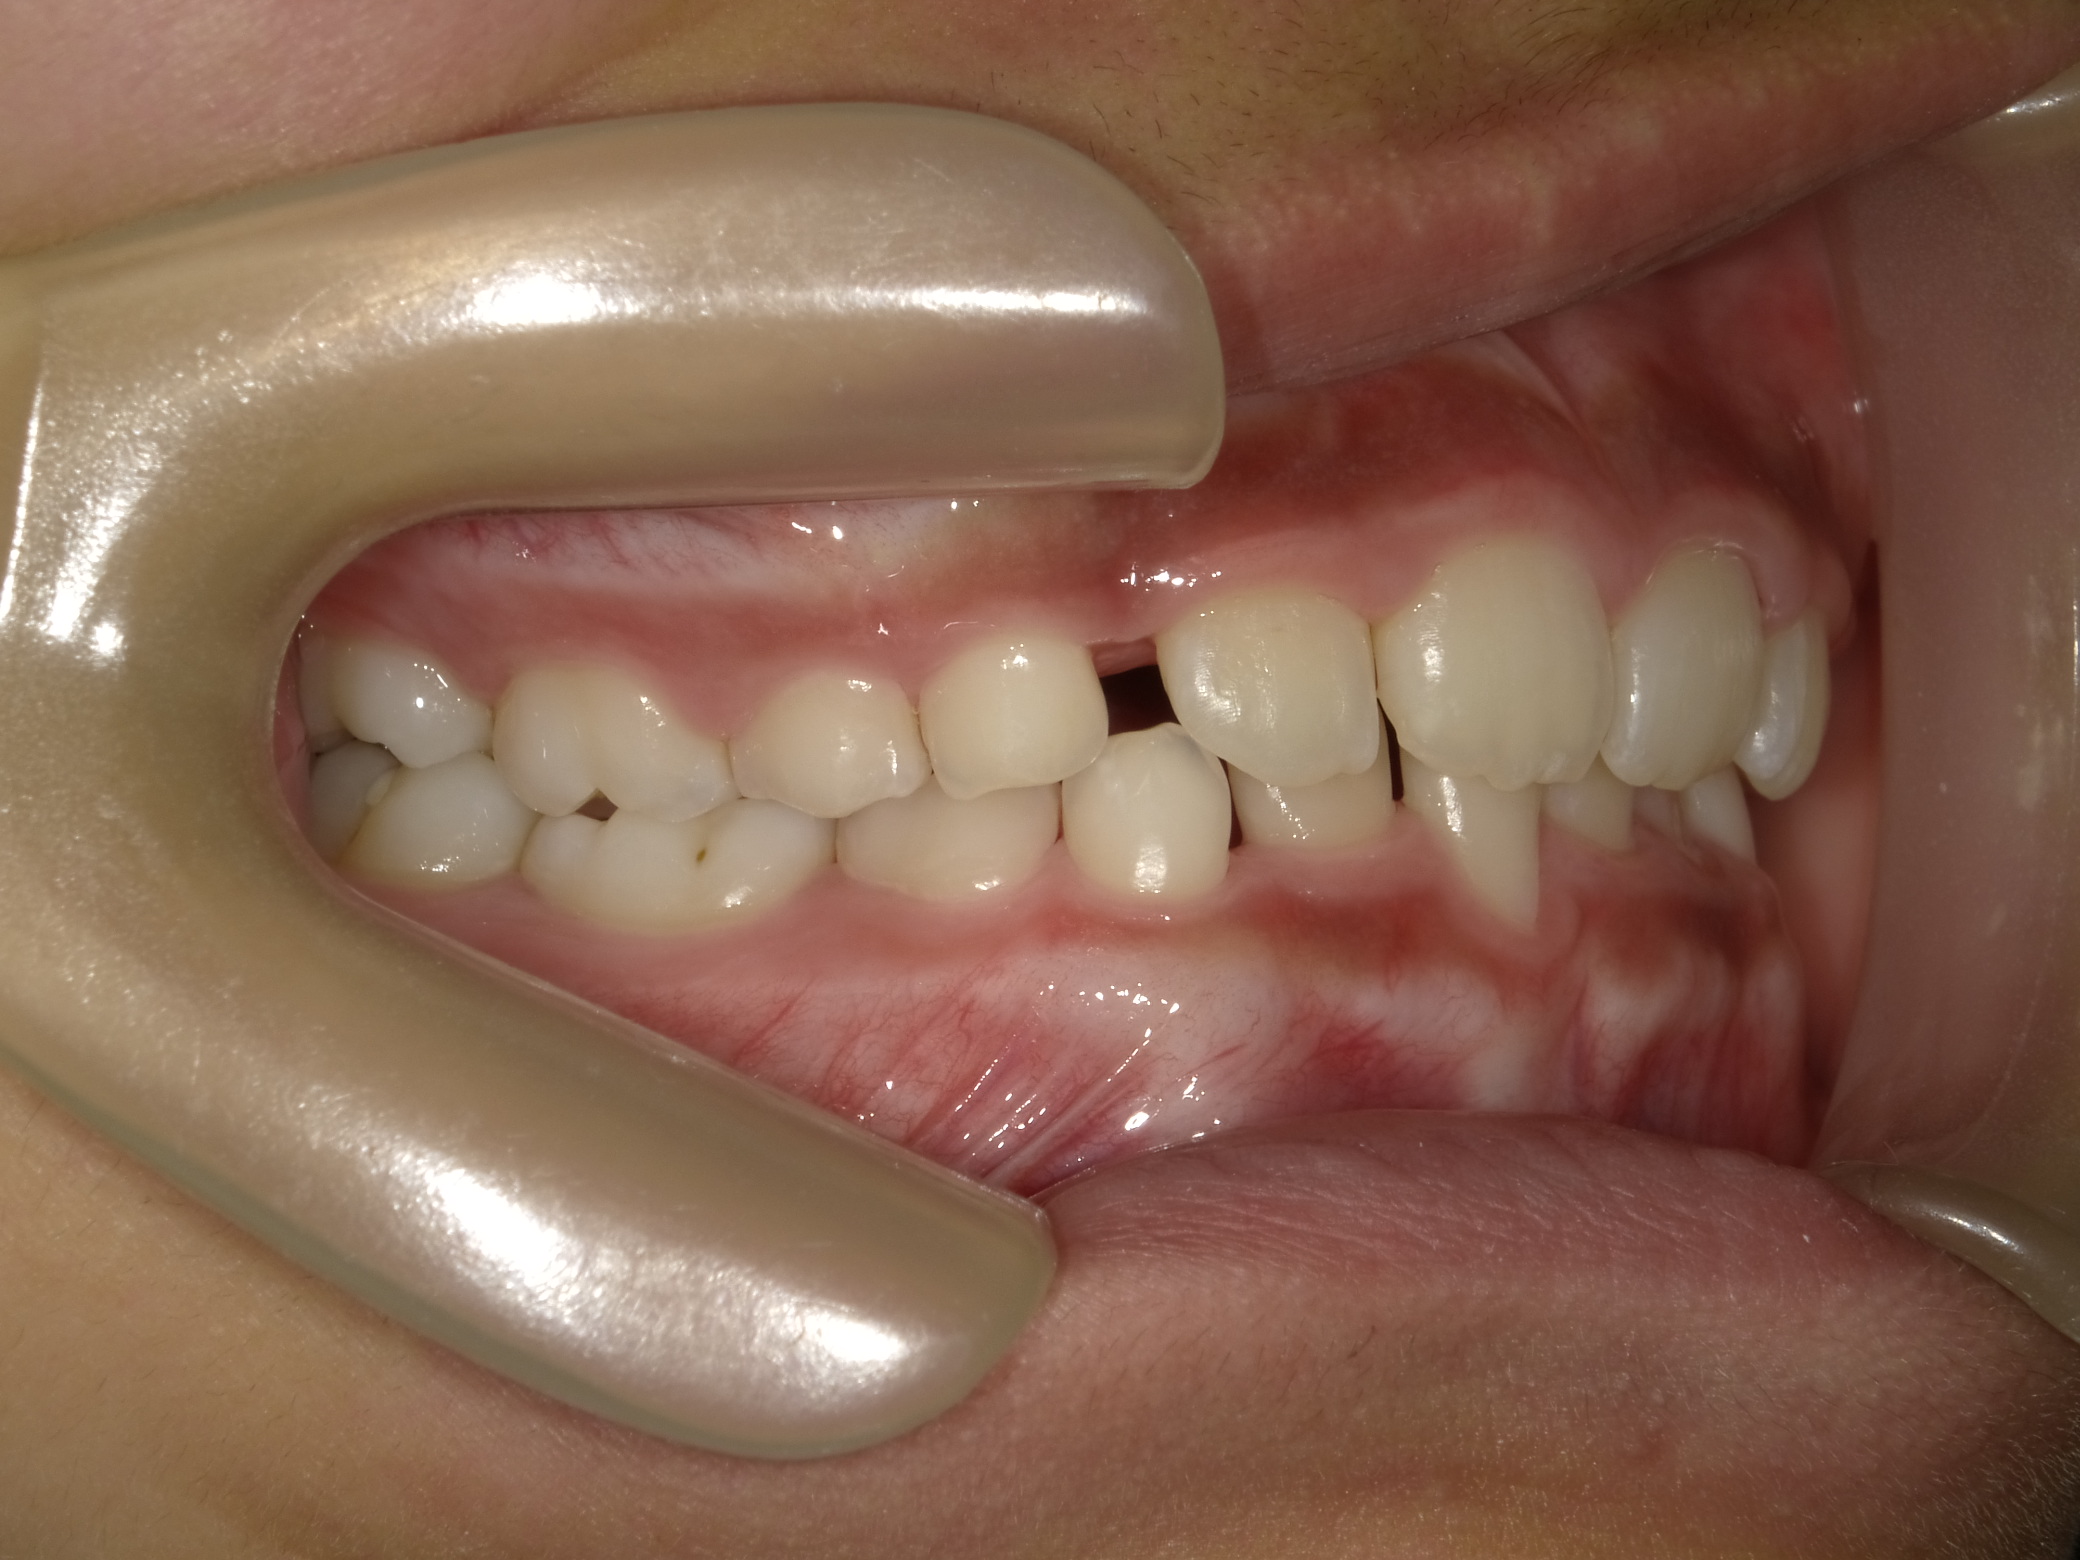

| 症例分類 | 交叉咬合 |

|---|---|

| 主訴 | 前歯がずれて咬んでいる |

| 年齢 | 9歳5ヶ月 |

| 性別 | 女性 |

| 抜歯部位 | なし |

| 使用装置 | 拡大装置、上顎前歯部のセクショナルアーチ装置、取り外し式保定装置 |

| 治療期間 | 1年2ヶ月 |

| 費用 | 相談料0円、検査料50,000円 動的矯正治療費330,000円 調整料6600円×15回分 保定装置料0円 |

| リスク・注意点 | 個々の歯の大きさに対して顎が小さく、歯が並ぶスペースが不足したために交叉咬合が生じています。これらを改善するために、幅の狭搾している歯列を側方に拡大した後、前歯を排列しました。

歯の動き方には個人差があり、予想された治療期間が延長する可能性があります。 治療中は矯正歯科装置が歯の表面に付いており、歯が磨きにくくなるため、むし歯や歯周病が生じるリスクが高まります。ハミガキを適切に行ってお口の中を常に清潔に保ち、さらに、かかりつけ歯科医に定期的に受診することが大切です。 矯正歯科装置の使用状況、定期的な通院など、矯正歯科治療には患者さんの協力が必要であり、それらが治療結果や治療期間に影響します。 治療の経過によっては当初予定していた治療計画を変更する可能性があります。 保定装置の装着時間が十分確保できない場合、歯並びや、咬み合せの「後戻り」が生じる可能性があります。 上下両側第二大臼歯の萌出を観察する必要があります。 |